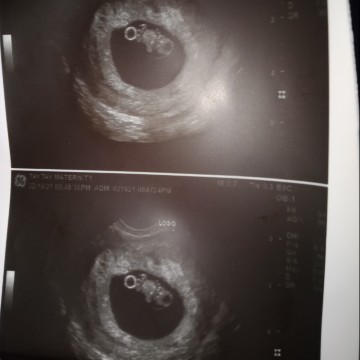

yan na c baby mag 10 weeks na kmi ni baby ko... hope n lumaki cia na malusog at maayos..😊